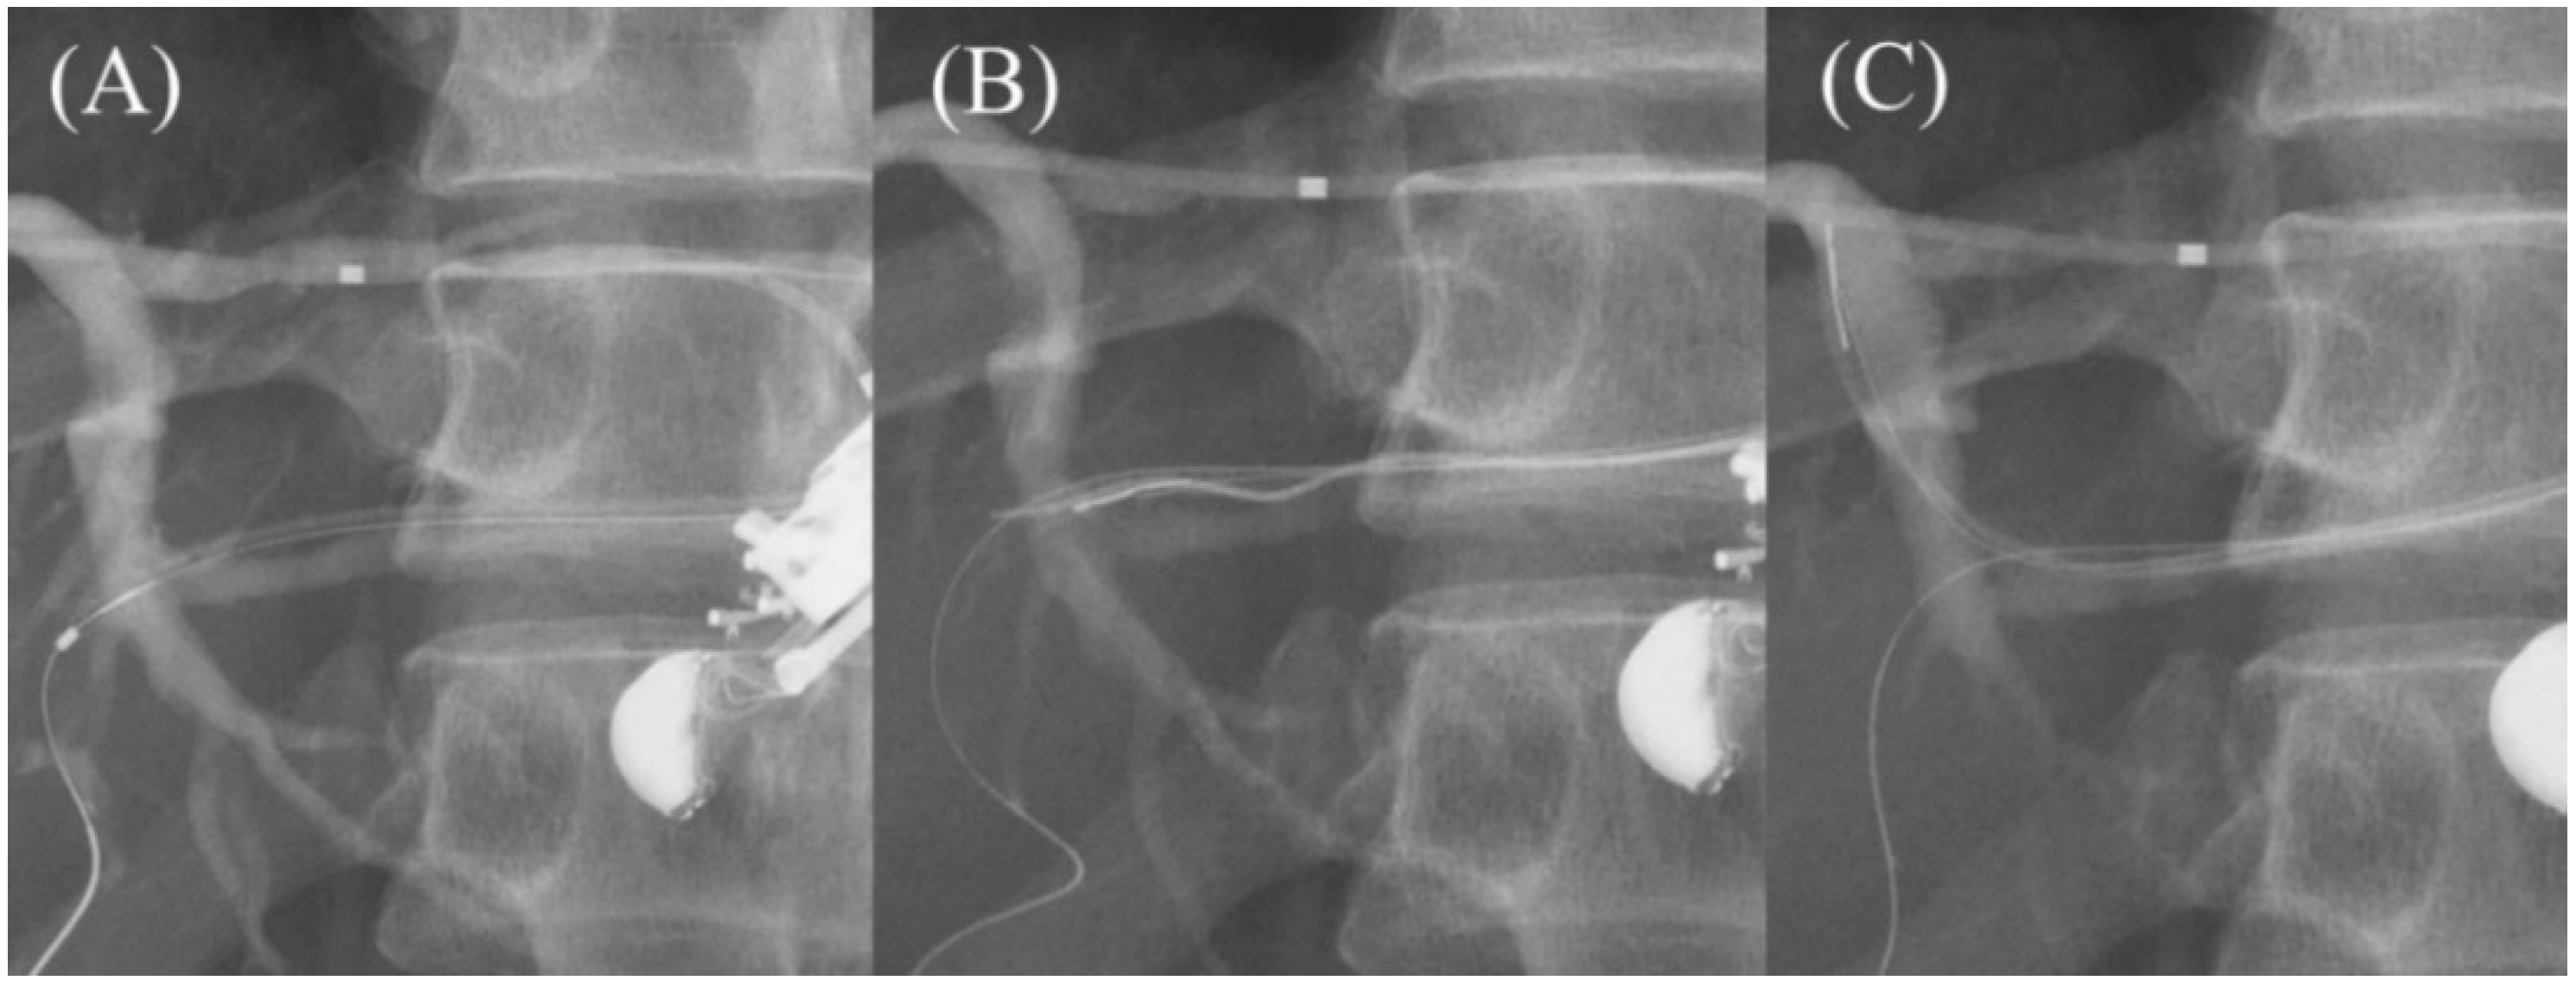

Currently, various types of SEMS are available for EUS-HGS with respect to stent design (braided or laser-cut type), coverage (partial or full), presence or absence of anti-migration properties at the gastric end, and size of the introducer. As a dedicated device for EUS-HGS, several partially covered braided SEMSs with anti-migration properties have been released by Korean companies (Figure 16A–D) [17,73,74,75,76,77,78,79]. In Japan, the most common SEMS for EUS-HGS is Niti-S S-type stent (modified Giobor stent; Taewoong Medical, Seoul, Korea), which is a partially covered SEMS with a 1 cm uncovered portion at the hepatic end [71,80]. Since this stent is a braided SEMS with a cross-wire structure, it gradually expands in the stomach from the non-expanded part in the gastric wall to form a smooth and gently sloping stent surface. Therefore, the effect of holding down the gastric wall is weak. Furthermore, the shortening rate of the stent is large, which tends to cause delayed migration of the gastric end into the peritoneal cavity (Figure 17A–C). In order to prevent this, the stent length should be longer than 10 cm, but even a long stent cannot prevent it completely as mentioned above. For this reason, Niti-S Spring Stopper Stent (Taewoong Medical) was developed with a spring-type stopper at the gastric end to prevent migration (Figure 18). This stent can reliably prevent delayed migration of the gastric end. Meanwhile, pre-dilation of the tract is usually required for these SEMSs insertion because the diameter of the introducer is 8.5 Fr.

Figure 17.

Impending delayed migration in Niti-S S-type stent (Taewoong Medical). A sufficient length of the gastric end of the stent is seen after the procedure (A). The next day’s CT shows that the intragastric stent length has shortened (B). Urgent endoscopy reveals impending migration of the gastric end of the stent (C).